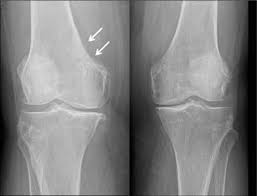

A térdizület kopása meglehetősen gyakori és nagy panaszokkal járhat. A folyamatot gyorsítja az ízület korábbi sérülése, instabilitása a testsúly felesleg.

Tünetei: a fájdalom, a mozgásbeszűkülés, az. un. indulási fájdalom, az ízületi folyadékgyülem, a deformitás.

A kezelés alapelvei: a folyamat lassítása, testsúlycsökkentés, rendszeres mozgás, ízületi porcregeneráló gyógyszerek, ízületi folyadékot pótló injekciók, az ízület artroscopos kitisztítása, korrekciós műtétek, ortézisek használata, fizikoterápia, végső esetben, ha már nincs más lehetőség, protézis műtét.

A térd betegségeinek vizsgálatában a fizikális vizsgálat, a röntgen, az ultrahang, a CT, és MR az alkalmazható vizsgálatok.